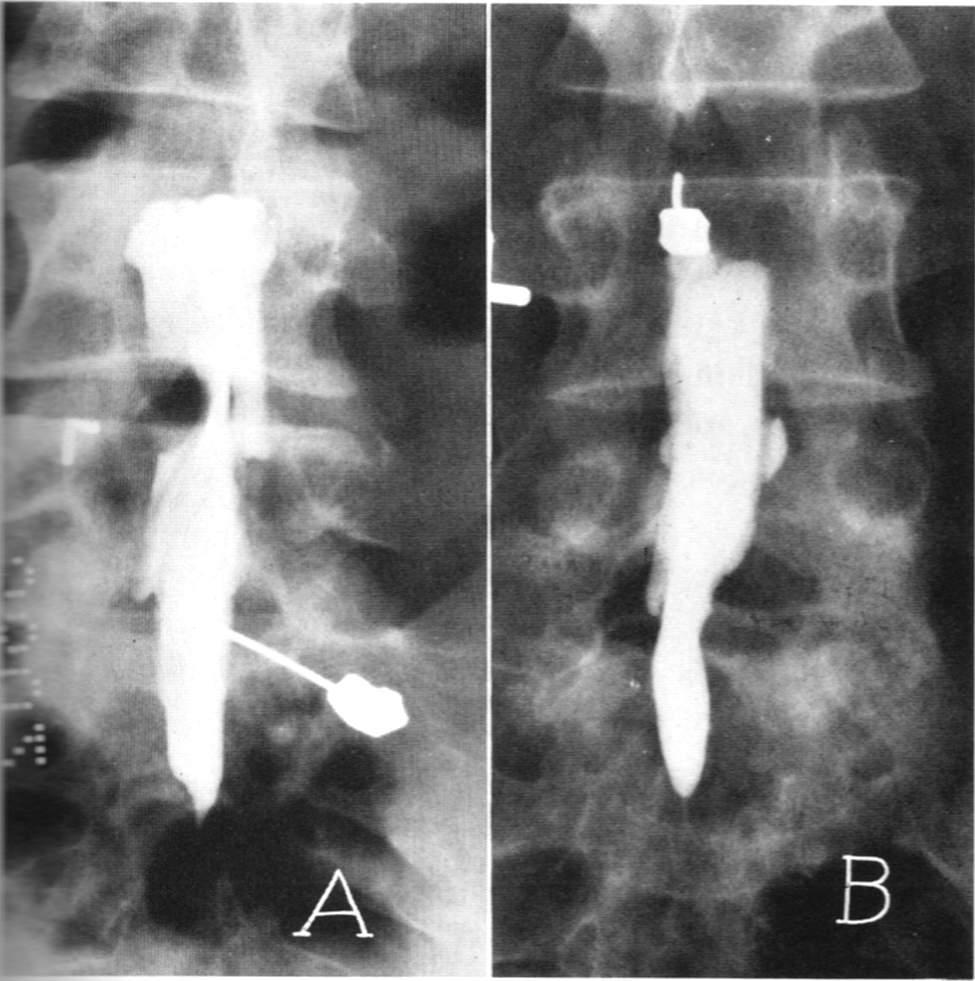

脊髓造影:往脊髓腔里面打造影剂后拍个片子,准确率可以达到80%,但无法良好的显示神经根,同时有创,一般很少用。

腰椎间盘突出针灸有副作用吗,腰椎间盘突出针灸越来越严重